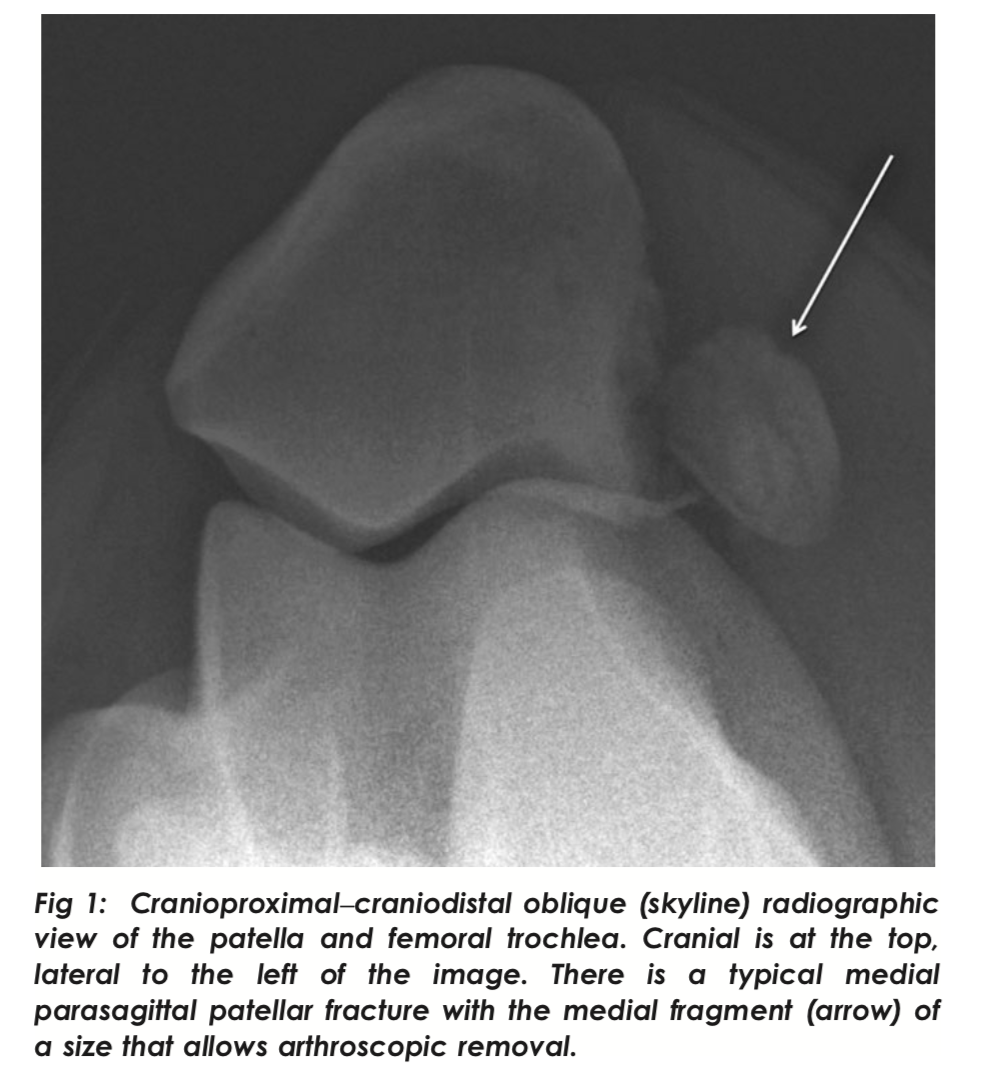

Most common patella fracture configuration

Medial parasagittal

Typically occur while the joint is in partial flexion e.g. when jumping over a fixed obstacle hunting or eventing. Patella is fixed against the trochlea in flexion so direct trauma causes contact with the more prominent medial trochlear ridge, hence fracture is medial of midline

Standard tx for medial parasagittal patella fractures and size limitations

Fragments lass than 1/3 of the size of the patella are best tx with ASY removal

Need to dissect free from medial patella lig, medial femoropatella lig and parts of the vastus medialis tendon